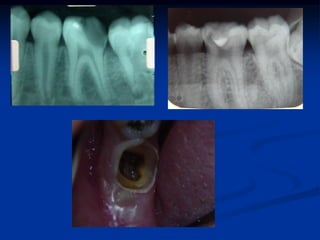

ENDODONTIA

Dentes vitais-

MTA

Mortificação

Retratamento

BONETTI et al. (2003)

1. RX Diagnóstico

2. Indicação terapêutica

Dentes com vitalidade, cav. profunda

com ou sem exposição pulpar....jovens.

3.Proteção próximo ou sobre a polpa

4.Base CIV

5.Rx proservação

6.Restauração